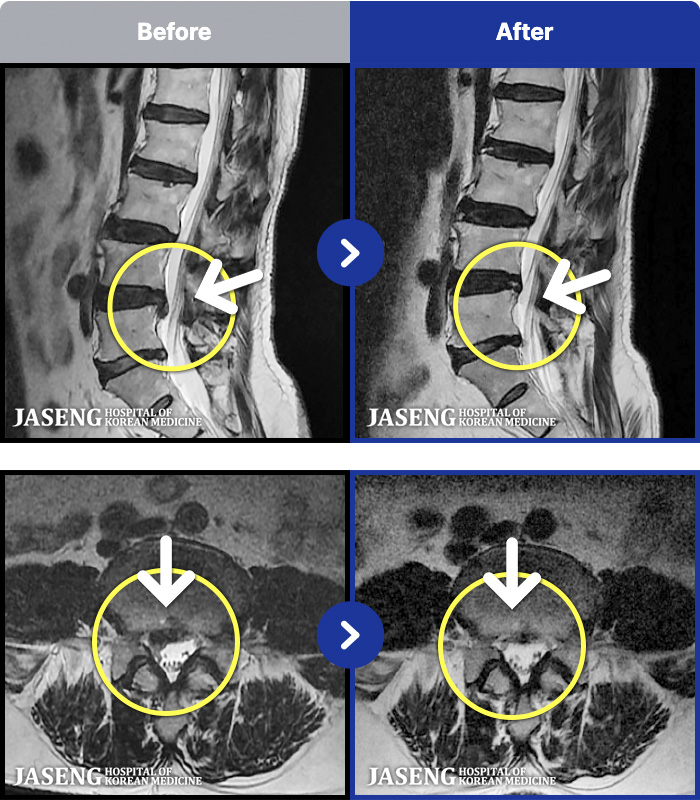

수술이 무서웠습니다… 그래서 다른 선택을 했습니다